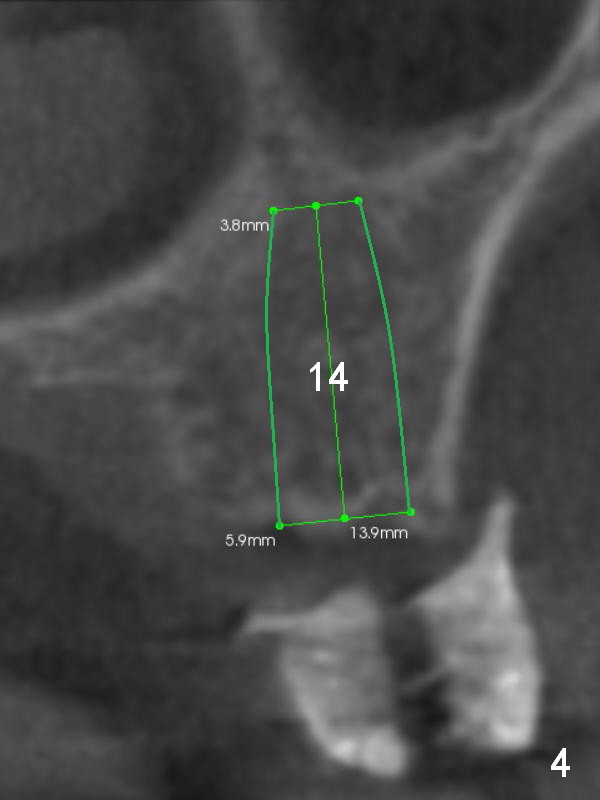

Three implants will be placed in the upper left posterior sextant (Fig.1-4). Without incision, place a surgical stent with trajectory tubes in place. Start osteotomy through the metal tubes (Fig.5,6) with a 2 mm pilot drill (SM) with drill extension if necessary. Palpate the buccal plate while drilling. Insert parallel pins for PA. According to the size of keratinized gingival band in the edentulous area, use either a 4 mm tissue punch or #15 scalpel for access. This way favors the trajectory over the diameter and length of the implants.